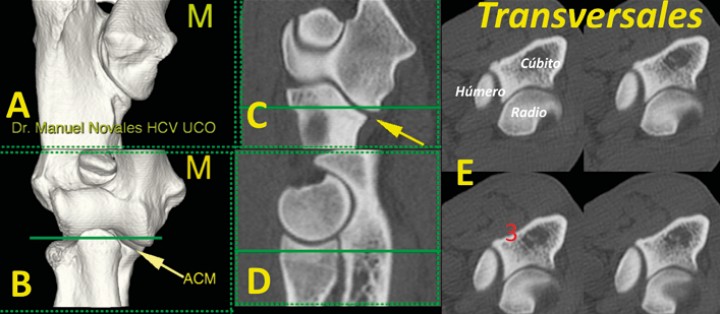

En el plano transversal nos fijamos sobre todo en la ACM, especialmente a dos niveles: a) a nivel del ápex que reconocemos por aparecer solamente dos huesos (el cúbito y el radio); b) proximalmente al ápex (donde aparecen los tres huesos, incluido el húmero). En este plano transverso es importante valorar: 1) la morfología del ápex (redondeada o puntiaguda, pero sin fragmentaciones, fisuras, cambios de densidad u osteofitos); 2) la escotadura (incisura) radial que tiene que mostrar una curvatura regular, sin alteraciones en su contorno y bien adaptada al radio; 3) la ausencia de reacciones óseas (esclerosis u osteofitos) en ninguno de los huesos implicados (Figs. 5 y 6) (Vídeo 2).

<p>Imagen tridimensional en visión caudomedial (<strong>A</strong>), craneal (<strong>B</strong>), así como en los planos dorsal (<strong>C</strong>), sagital (<strong>D</strong>) y transversales (<strong>E</strong>) a nivel de la ACM (flecha) señalado en las líneas verdes (C y D). En estos planos valoramos el ápex (1) y la incisura radial (2) (M: lado medial).</p>

Imagen tridimensional en visión caudomedial (A), craneal (B), así como en los planos dorsal (C), sagital (D) y transversales (E) a nivel de la ACM (flecha) señalado en las líneas verdes (C y D). En estos planos valoramos el ápex (1) y la incisura radial (2) (M: lado medial).

<p>Imagen tridimensional en visión caudomedial (<strong>A</strong>), craneal (<strong>B</strong>), así como en planos dorsal (<strong>C</strong>), sagital (<strong>D</strong>) y cuatro cortes transversales (<strong>E</strong>) a nivel de la ACM (flecha) señalado en las líneas verdes (C y D). En la imagen B se aprecia como la línea de corte (verde) pasa por los tres huesos del codo. En esta imagen valoramos la ausencia de reacción ósea (3) (esclerosis u osteofitos). (M: lado medial).</p>

Imagen tridimensional en visión caudomedial (A), craneal (B), así como en planos dorsal (C), sagital (D) y cuatro cortes transversales (E) a nivel de la ACM (flecha) señalado en las líneas verdes (C y D). En la imagen B se aprecia como la línea de corte (verde) pasa por los tres huesos del codo. En esta imagen valoramos la ausencia de reacción ósea (3) (esclerosis u osteofitos). (M: lado medial).